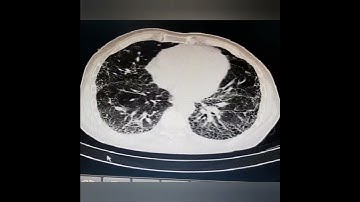

Recognizing Common CT Imaging Signs of Lung Diseases through a New Feature Selection Method based on